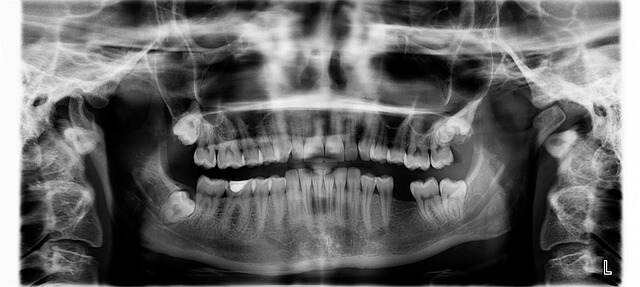

*임플란트 뼈이식 비용을 실손보험으로 청구하려면 몇 가지 준비물이 필요해요. *첫째, 치과에서 발급받은 진료기록서와 시술 내역이 상세히 기재된 영수증이 가장 중요합니다. *임플란트 뼈이식 관련 진단명이나 수술명이 정확히 적혀 있어야 보험 심사 과정에서 누락되지 않아요. *제가 실제로 겪어본 경험으로는 X-ray나 CT 영상 자료도 함께 준비하면 청구가 훨씬 수월해지더군요. *이처럼 꼼꼼한 서류 준비가 임플란트 뼈이식 실손보험 청구의 핵심 포인트입니다.